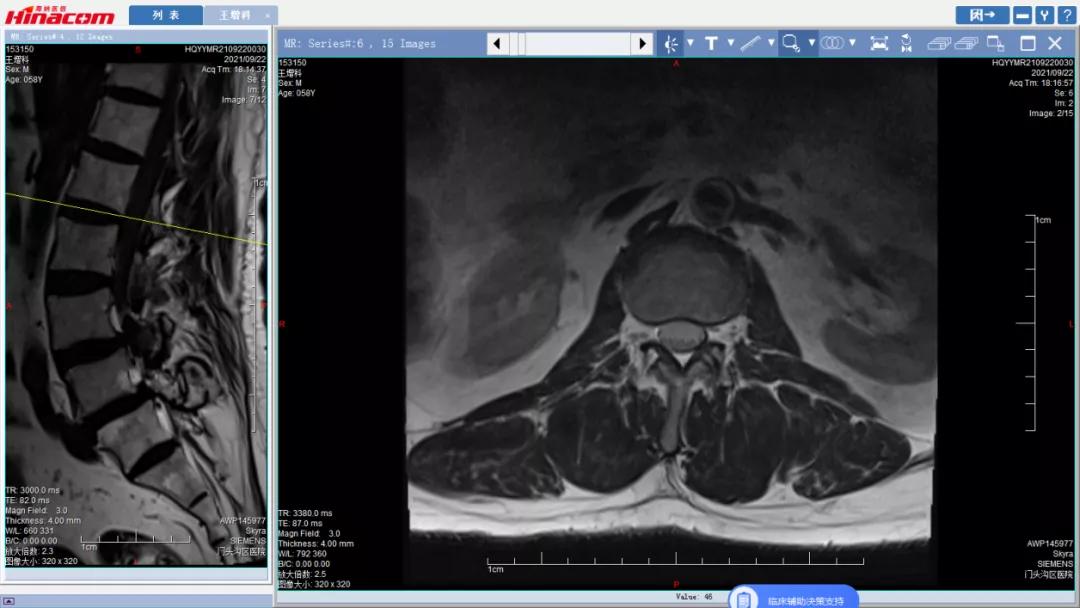

腰椎管矢状面--术前MRI

腰34椎管水平面--术前MRI

腰45椎管水平面--术前MRI

正常腰椎管水平面--术前MRI